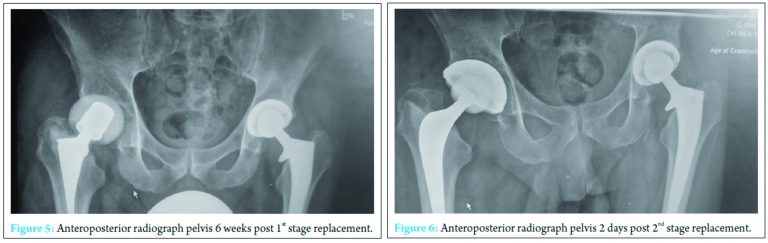

At 2 weeks, the onset of wound ooze and rising markers prompted a repeat washout. Intraoperative samples on this occasion were positive for Pseudomonas aeruginosa and S. aureus prompting the addition of IV piperacillin-tazobactam 4.5 g TID and IV gentamicin 400 mg OD to the IV flucloxacillin and oral sodium fusidate treatment. The patient responded clinically and biochemically with resolution of pain, the absence of pyrexia and a reduction in inflammatory markers to a white cell count of 13 × 103 cells/mm3 and CRP of 41 mg/ml. Despite this positive response, however, the wound ooze persisted (Fig. 3).

A further washout performed at week three revealed a deep fluid collection so the wound was left open and a vacuum-assisted closure (VAC) device applied. Six separate theater specimens were all negative for microbial growth. Following this, the Microbiology Department advised discontinuing IV piperacillin-tazobactam and IV teicoplanin 400 mg TID and meropenem 1 g TID were commenced. Throughout the first few weeks, alternative sources of infection including endocarditis were excluded and a magnetic resonance imaging revealed no pelvic collection or evidence of osteomyelitis. The VAC drainage remained high and further theater wound inspections identified the deep collection was not recurring. One of the deep tissue samples sent in this period was positive for C. albicans. Although initially thought to be a contaminant, oral fluconazole 400 mg OD was commenced given the poor response to polymicrobial therapy. Despite remaining clinically and biochemically well, the wound failed to progress, and therefore a formal first stage excision arthroplasty was performed 8 weeks following admission, with a Biomet stage one select reinforced cement hip spacer impregnated with gentamicin and vancomycin through an anterolateral approach [7] (Fig. 4). Femoral head histopathology confirmed appearances in keeping with osteomyelitis. Throughout the next 2 weeks, four changes of VAC were required to monitor the wound and ensure no deep collection was persisting, due to a pattern of fluctuating inflammatory markers. Positive C. albicans cultures were obtained from only two out of nine deep tissue samples taken intraoperatively despite the patient being on antimicrobial therapy. Peripheral blood cultures remained negative. A diagnosis of secondary fungal septic arthritis was then made given the recurrent positive C. albicans growth from tissue samples. Oral fluconazole 400 mg OD was escalated to intravenous anidulafungin 50 mg OD and antibiotic therapy discontinued following a 10-week course (Fig. 5). He responded well both clinically and biochemically with a white cell count of 10 × 103 cells/mm3 and CRP of 30 mg/ml. The wound settled slowly and progressively thereafter allowing delayed primary closure 9 weeks following admission. Following wound closure, he remained well with a healing wound and therefore was discharged home on his intravenous antifungal treatment. An uncomplicated second stage procedure was performed 3 months following the first stage procedure with implantation of a cemented total hip replacement. Revision copal cement, impregnated with gentamicin and clindamycin as standard was supplemented with 600 mg grams of anidulafungin antifungal powder [8] (Fig. 6).